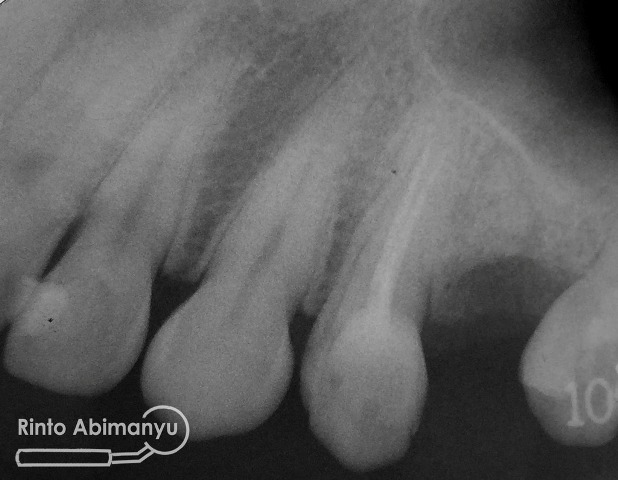

Tampilan setelah pengisian…

Untuk coronal seal memakai low shrinkage stress flowable composite SDR (Dentsply) dan atasnya ditutup dengan komposit packable….

Pengambilan ronsen dilakukan pada gigi tersebut…

Alhamdulillah rangkaian perawatan bisa selesai dalam satu kunjungan sehingga pasien tidak terlalu repot dan bisa melanjutkan perawatannya di sejawat pengirim… π